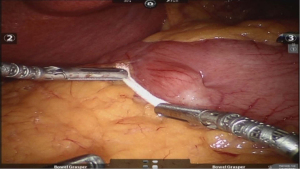

After placing the ports and the liver retractor, a thorough diagnostic laparoscopy is done. Omentum and transverse colon is lifted up to expose small bowel, and the duodeno-jejunal flexure/ligament of Trietz is identified. 75 cm of small bowel is measured from DJ flexure and it is hitched to stomach near lesser curvature at two sites using non absorbable sutures (Figure 3). Here, one should take care to keep proximal loop (biliopancreatic limb) on left side of patient. Beyond that point, another 100 cm of small bowel is measured distally and marked using non-absorbable suture at two sites 5 cm apart keeping proximal stitch small and distal stitch longer.